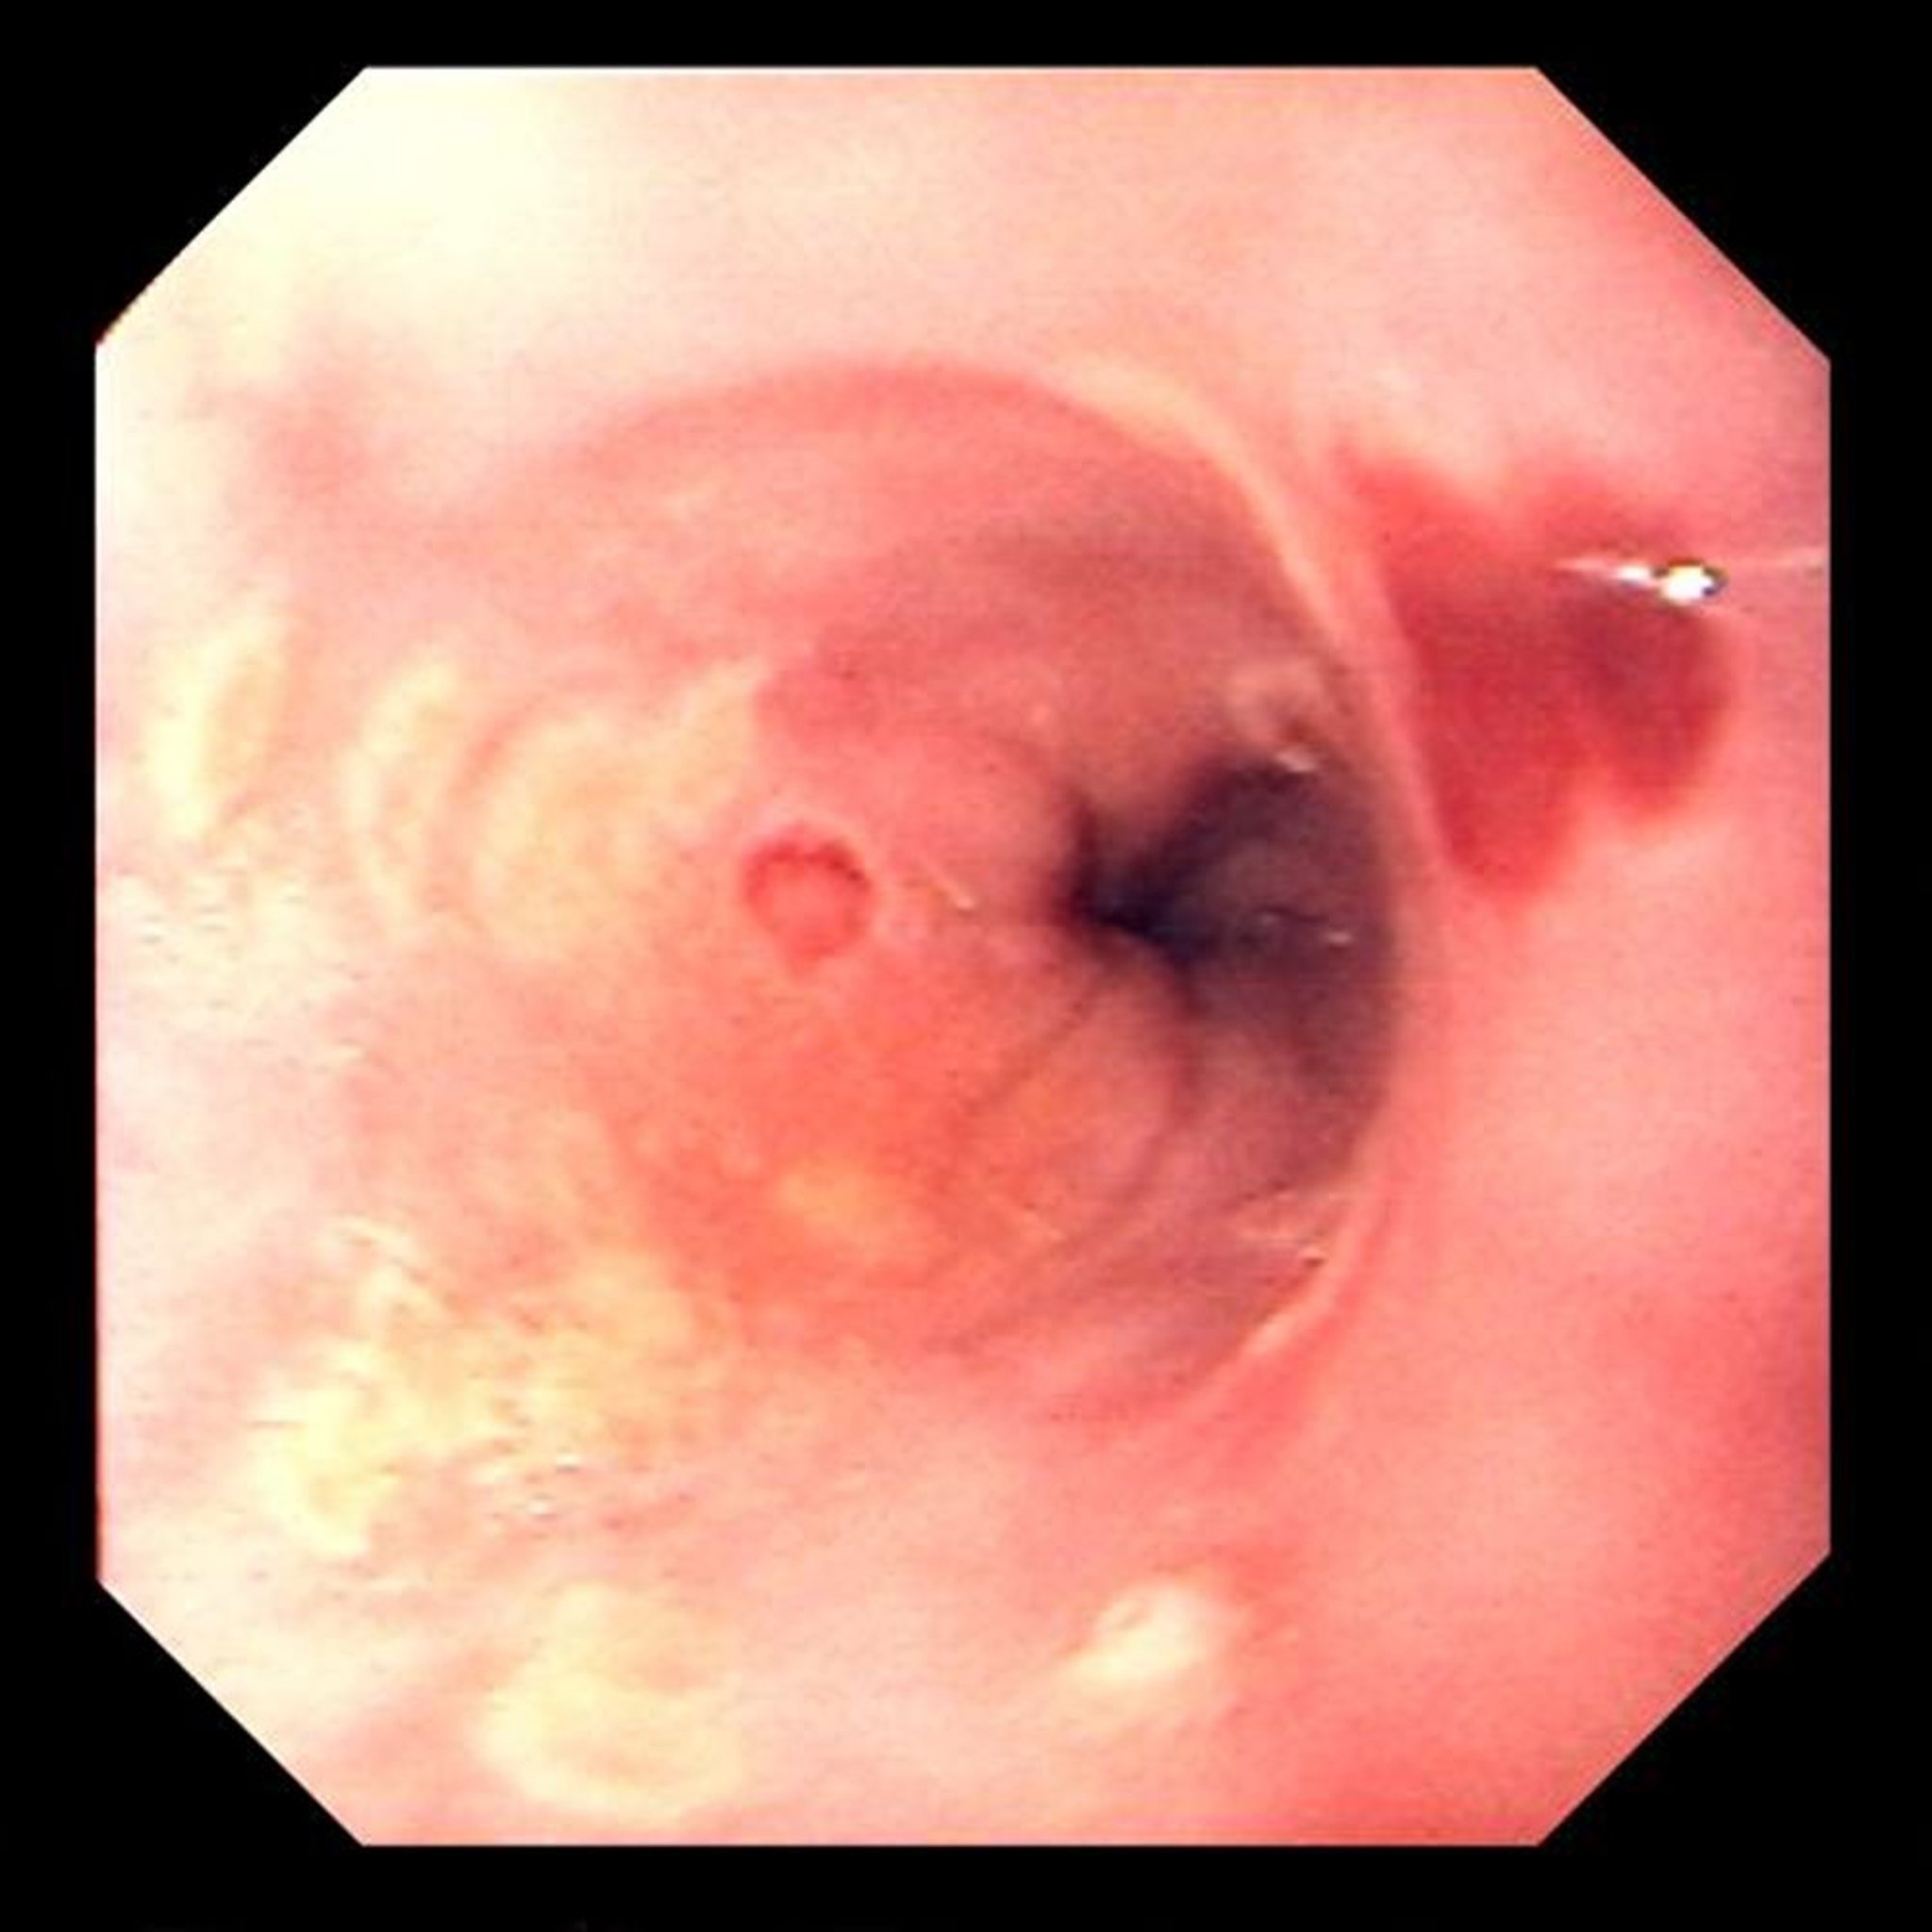

Esofagite da herpes simplex

Le ulcerazioni focali sono tipiche dell'esofagite da virus dell'herpes simplex.

Image provided by David M. Martin, MD.